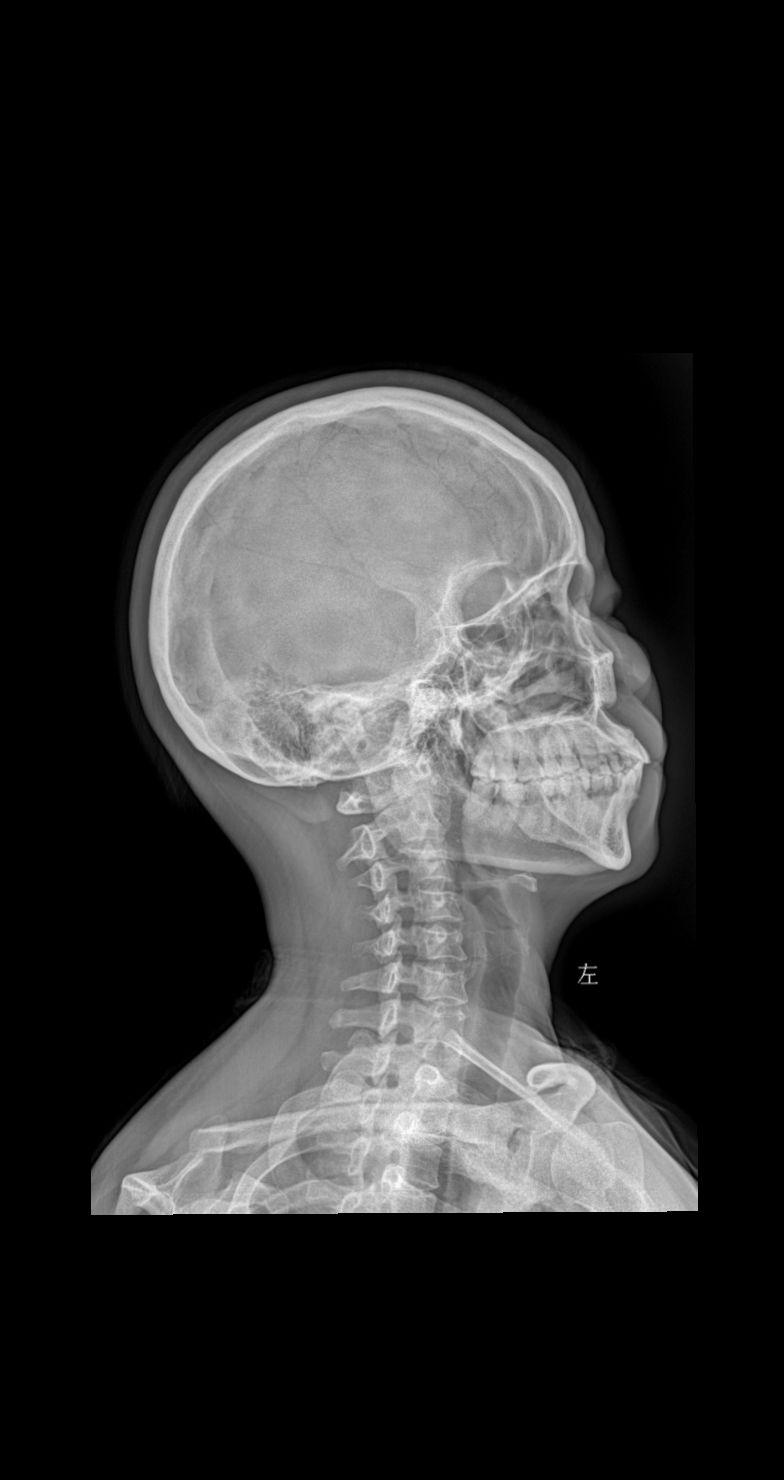

颈部疼痛 头晕 就诊